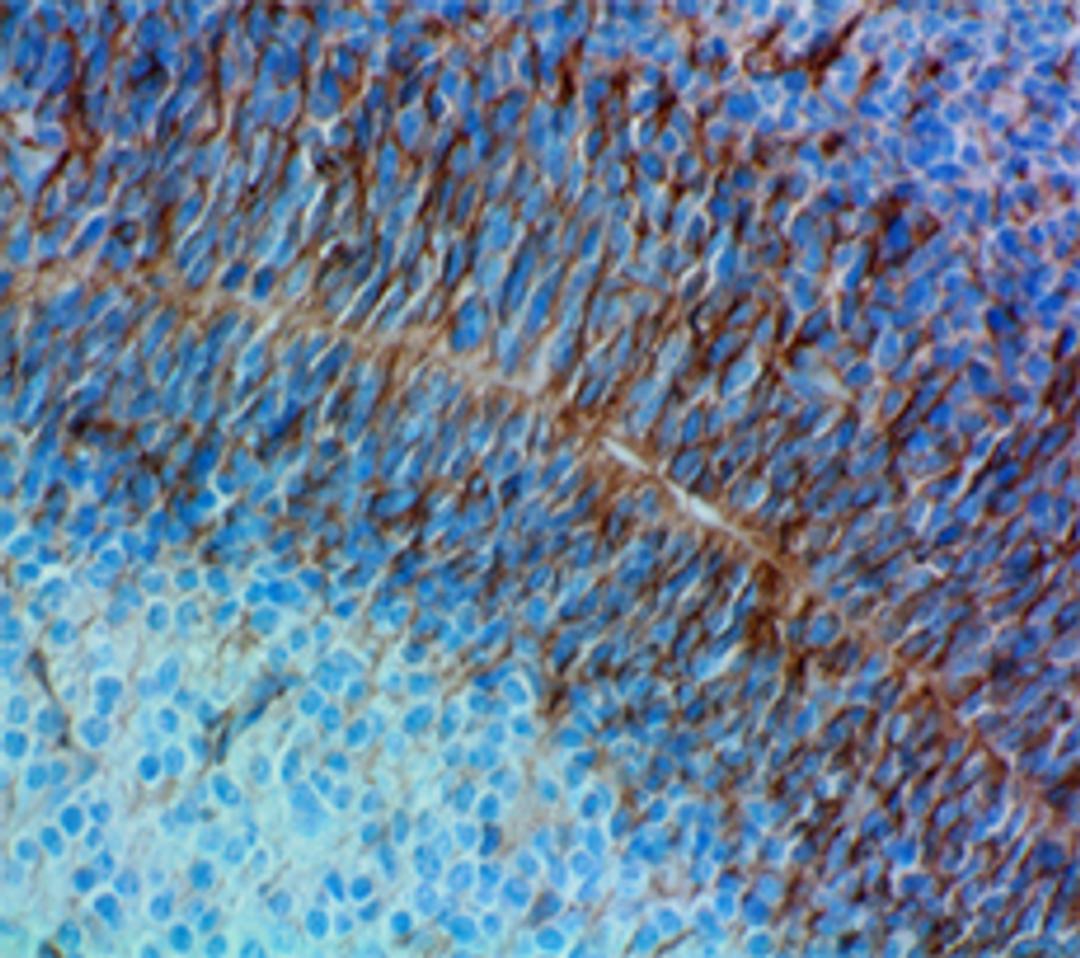

HRP anti-Nestin; Clone: Rat-401; Reactivity: Mouse, Rat; Apps: IHC-P; Size: 100 μg